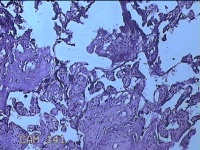

胎盘组织

性别

女

年龄

30岁

临床诊断

妊娠合并中度贫血

一般病史

停经39+2周,B超检查发现羊水偏少6小时。

标本名称

大体所见

灰白暗红色胎盘组织16.5x14.5x3.5㎝一个,表面光滑,血管突出,颜色发暗,绒毛面结节状,有轻度糜烂,暗红色,有少许凝血块,切面见绒毛内有暗红色血液渗出,边缘蜕膜可见多个小血肿,脐带39x1.8x0.3㎝,螺旋状扭曲,切断脐带,见脐血管内有凝血块。